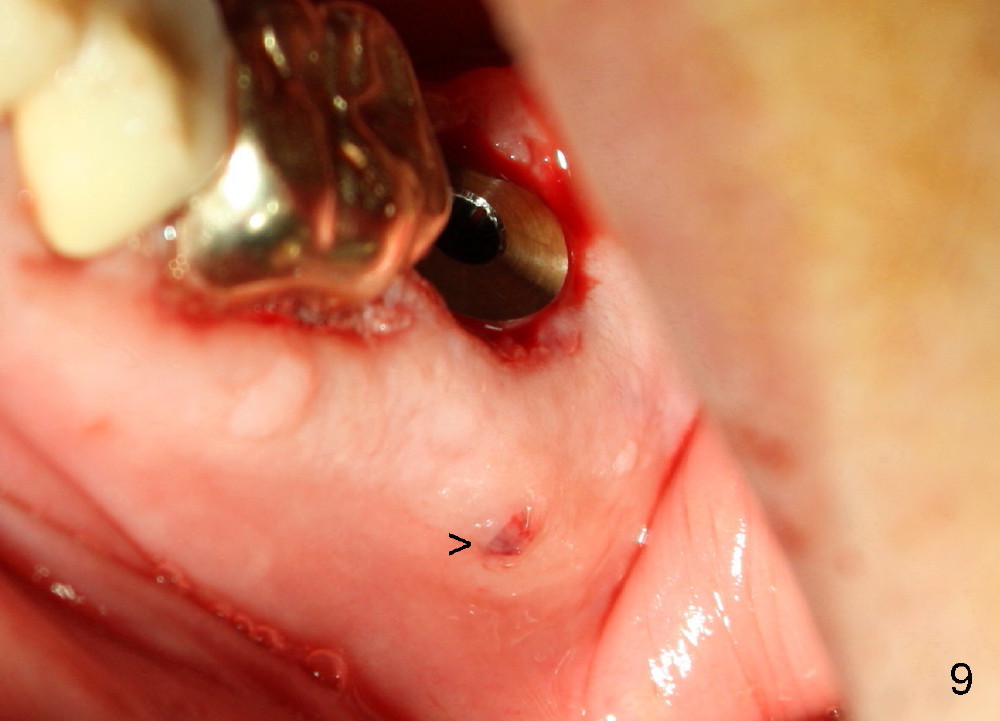

Prior to implant placement (Fig.7,9: 7x17 mm with insertion torque 40 Ncm), a mixture of autogenous bone (Fig.8 red particles) and demineralized cortical allograft (white granules) is packed against defective socket walls, particularly apically. It leaves a space in the middle of the socket for implant insertion later on. In this case, the buccal wall around the apex, corresponding to the fistula (Fig.9 >) is severely destroyed, whereas the crestal portion is more or less intact. Three months later, the implant appears yet to osteointegrate (Fig.10), while the fistula disappears (Fig.11). The large implant does not look too overengineered over the alveolus (Fig.12 (lingual view). In fact, the implant has mild mobility. How to fix it?